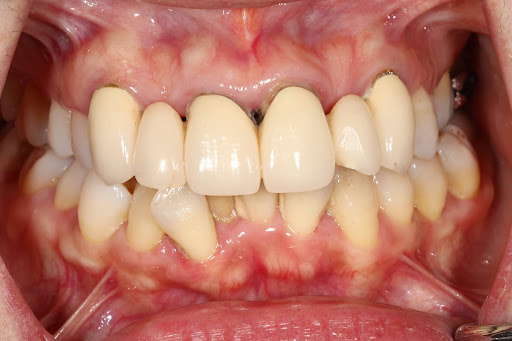

見た目の美しさだけでなく、噛みやすさや耐久性にも配慮した“機能美”という考え方

私たちは「機能美」という考え方のもと、

見た目の美しさだけでなく、

噛みやすさ、耐久性、メンテナンス性まで含めたトータルな美しさを追求しています。

「見た目が美しい治療は長持ちする」

という“機能美”へのこだわり